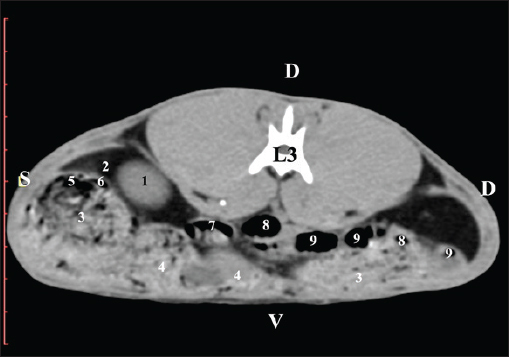

Fig. 9. Pre-contrast computed tomography (CT) anatomical scan of the regio-abdominis media at the caudal L3 edge level. (1) Ren dexter; (2) adipose collections; (3) cecum; (4) colon ascendens; (5) jejunum; (6) pars ascendens of the duodenum; (7) colon descendens. The pre-contrast anatomical scan at the L4 level provided data about the location of the renal pelvis within the renal sinus. The initial part of the pelvis renalis appeared as a distinct funnel-shaped hypoattenuated soft tissue, whose central part was widened and formed the recessus renalis. The transition of the narrowed end of the renal pelvis into the hypoattenuated left ureter was without a sharp boundary. The left kidney was in contact with the cecum, colon ascendens, and colon transversum ventrally. Crista renalis was observed as a hypoattenuated linear soft tissue finding (Figs. 10 and 11).

Fig. 10. Pre-contrast computed tomography (CT) anatomical scan of the regio-abdominis media at the cranial L4 edge level. (1) Ren sinister; (2) pelvis renalis and crista renalis; (3) ureter; (4) cecum; (5) colon ascendens; (6) colon transversum; (7) colon descendens; (8) adipose collections.